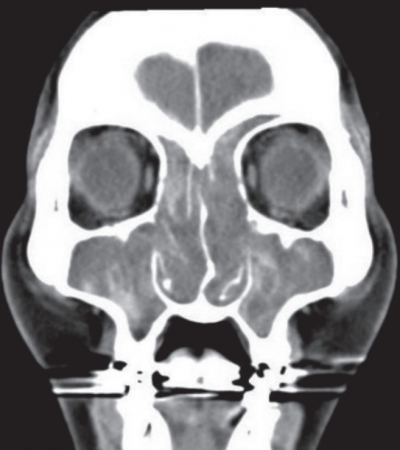

48 歳の女性。鼻閉を主訴に来院した。数年前から鼻閉と嗅覚低下があり、風邪をひくと悪化した。鎮痛薬で気管支喘息を起こしたことがあった。左鼻腔の内視鏡像を別に示す。右鼻腔も同様の所見である。副鼻腔単純 CT の水平断像と冠状断像を別に示す。

慢性副鼻腔炎の症例。

内視鏡下鼻副鼻腔手術は、慢性副鼻腔炎や鼻茸に対して広く行われる治療法で、症状の改善と機能の回復を目的としている。

内視鏡を使用することで副鼻腔内の病変に直接アクセスし、鼻茸の除去や排液の改善を行う。